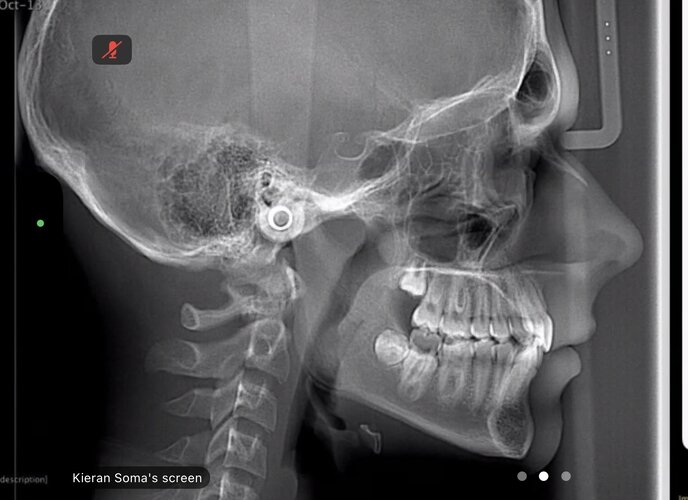

I have been recommended by the orthodontist to get my back left molar removed and potentially my wisdom teeth. He then said i should get 3 years of braces and some other shit. I feel like this is all bull shit, and he just wants to extort my parents' money. He said that because my back left molar is not coming through, my jaw could not be developing, but this contradicts everything I have seen on here with teeth extractions leading to recession. Could someone please help me